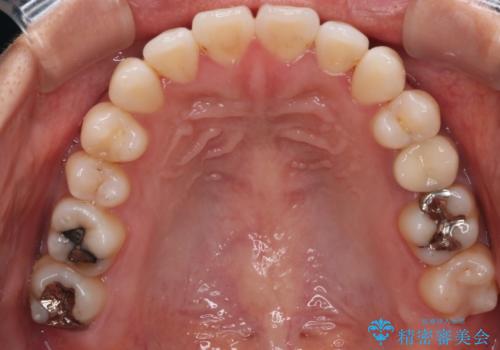

- 開咬を主訴に来院されました。前歯部に開咬、右側大臼歯部にクロスバイトが認められます。ワイヤー矯正の審美装置で治療し、ゴム掛けを行いながら噛み合わせを改善しました。

主訴である開咬と右側大臼歯部クロスバイトを改善でき、しっかりと噛むことができるようになりました。